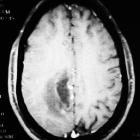

CT

Tumefactive demyelinating lesions appear as a large hypoattenuating lesion with ill-defined ring enhancement, central necrosis, perilesional edema and minimal mass effect .